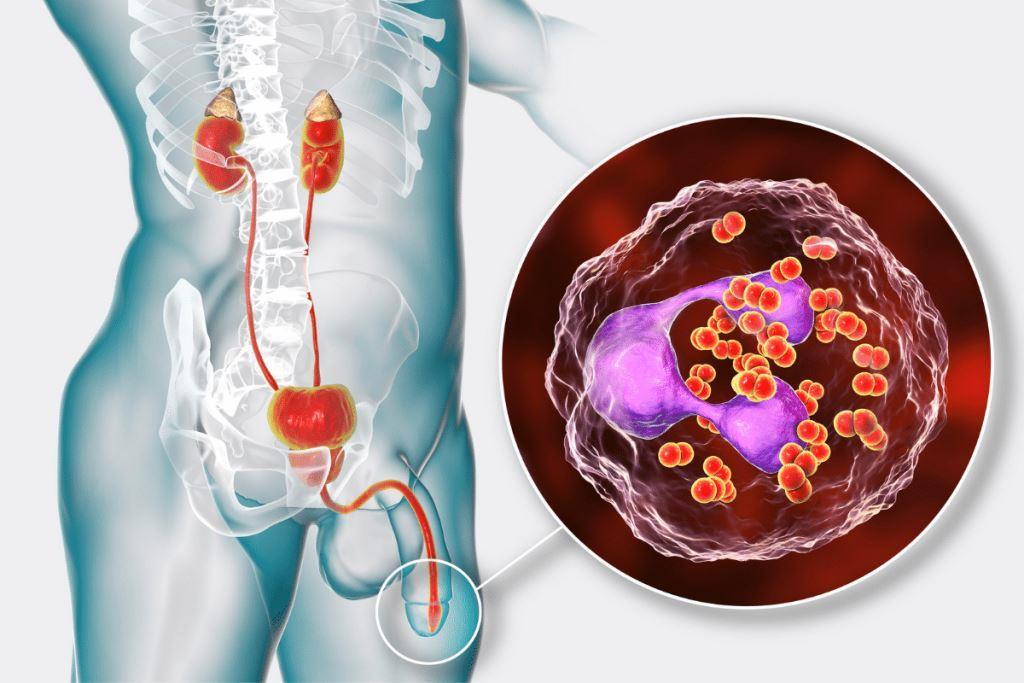

Bahaya Kencing Nanah, Ancaman Serius Bagi Pria dan Wanita

Obat Kencing Keluar Nanah – Kencing sakit keluar nanah atau cairan tidak normal berwarna putih, kuning, hijau atau bahkan bercampur darah merupakan tanda seseorang menderita gangguan penyakit kelamin. Kondisi ini tidak bisa dibiarkan begitu saja. Bahayanya bisa menyebabkan penyakit menular seksual (PMS) yaitu Infeksi gonore atau raja singa.

Gejala Kencing Nanah Pada Pria

- Keluar cairan berwarna dari ujung penis

- Rasa nyeri atau terbakar saat BAK

- Pembengkakan pada testis

- Demam disertai badan meriang

- Kencing terasa sakit & tersendat

APA PENYEBAB KENCING NANAH?

Obat Kencing Nanah – Penyebab kencing nanah adalah adanya Infeksi bakteri yang apabila tidak segera ditangani akan berbahaya menyebar ke organ tubuh lain seperti dub*r, Uretra pada pria, serviks pada wanita, tenggorokan hingga mata.

APA BAHAYA KENCING NANAH?

- Infeksi Saluran Kencing (Uretritis)

- Epididimitis

- Pembengkakan pada kelamin

- Menyebabkan kanker

- Meningkatkan Risiko Tertular HIV/AIDS

- Impotensi / lemah syahwat

- Gangguan fungsi ginjal

- Menyebabkan KEMANDULAN